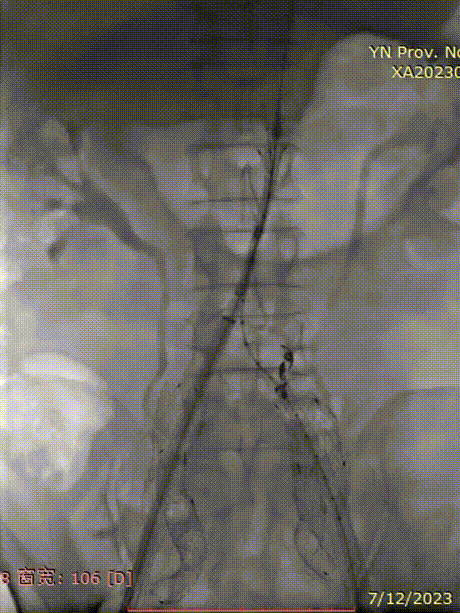

最后造影

支架锚定位置如预期,隔绝良好,无明显内漏;双侧髂内动脉血供得以保留,血流通畅。

五、术后一周复查CT

术后一周复查:支架位置合适、形态良好,双侧髂内血供得以保留;无内漏。